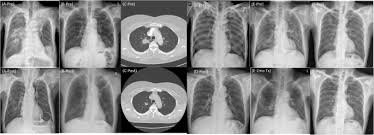

Lung cancer is often divided into two types: Lung cancer is the leading cause of cancer death worldwide, with approx. Tuberculosis (tb) is caused by bacteria (mycobacterium tuberculosis) that most often affect the lungs. Tuberculosis (tb) is a contagious infection that usually attacks your lungs. Lung cancer is most often discovered by mistake if it is detected in the early stages.

Since mycobacterium tuberculosis (mtb) is an intracellular organism, bacterial dna could integrate to bronchial epithelial cells inducing neoplastic transformation. 90% of cases being attributable to smoking. Lung cancers are generally divided into 2 main categories: Is it possible for the doctor to mistake a possible lung cancer for tb? Can lung cancer be found early? Even when lung cancer does cause symptoms, many people may mistake them for other problems, such as an. When lung cancer is suspected, a physician will perform a thorough history and physical exam. The occurrence of pulmonary tuberculosis (ptb) and lung cancer as comorbidities has been extensively discussed in many studies. The incidence of both conditions remains high in many developing countries, especially in east asia. In the past, it was well known that lung cancer is a specific epidemiological successor of ptb and that lung cancer often develops in scars caused by ptb. Living with advanced breast cancer. Pulmonary tuberculosis and lung cancer. Lung cancer is most often discovered by mistake if it is detected in the early stages.

Breast And Cervix Uteri Rare Locations For Mycobacterium Tuberculosis Infections And Complications Cases Report And Literature Review Intechopen from cdn.intechopen.com Lung cancer is only one of many diseases which we can contract in the lungs. Even if a mass is found, it may not be cancerous, and further studies are required to confirm its status. Symptoms of tuberculosis and lung cancer are overlapping and it is difficult to differentiate without the histopathological report. When people with lung tb cough, sneeze or spit, they propel the tb germs into the air. This is one reason that it is among the most deadly of cancer groups. Pulmonary tuberculosis (tb) may coexist with lung cancer and share some similarities with these conditions. Tb and lung cancer have been confused and misdiagnosed for centuries 2. 90% of cases being attributable to smoking.

When lung cancer is suspected, a physician will perform a thorough history and physical exam. Pulmonary tuberculosis (tb) may coexist with lung cancer and share some similarities with these conditions. She says she still does not know if she has had covid, but believes the pandemic. When people with lung tb cough, sneeze or spit, they propel the tb germs into the air. Tuberculosis (tb) is caused by bacteria (mycobacterium tuberculosis) that most often affect the lungs. Tb and lung cancer have been confused and misdiagnosed for centuries 2. Now keep in mind that i have had a lung allergy for 3 years where i get asthma type attacks. The occurrence of pulmonary tuberculosis (ptb) and lung cancer as comorbidities has been extensively discussed in many studies. Patients with lung cancer are often misdiagnosed as pulmonary tuberculosis leading to delay in the correct diagnosis as well as exposure to inappropriate. Tuberculosis (tb) is a contagious infection that usually attacks your lungs. Tuberculosis germs don't thrive on surfaces. Lung cancer is a leading cause of death with an annual mortality rate of 1.59 million people, accounting for 19.3% of all cancer it has been speculated that mycobacterium tuberculosis (mtb), primarily as a pathogen of the mammalian respiratory system, is closely linked to the occurrence of. Lung cancer, also known as lung carcinoma, is a malignant lung tumor characterized by uncontrolled cell growth in tissues of the lung.

Care guide for lung cancer. Lung cancer is the leading cause of cancer death worldwide, with approx. Possible causes, signs and symptoms, standard treatment options and means of care and support. Patients with lung cancer are often misdiagnosed as pulmonary tuberculosis leading to delay in the correct diagnosis as well as exposure to inappropriate. 7 incidence the incidence of lung cancer in tuberculosis patients was about 2%.

Possible causes, signs and symptoms, standard treatment options and means of care and support. Tb is spread from person to person through the air. When people with lung tb cough, sneeze or spit, they propel the tb germs into the air. The bacteria that cause tuberculosis are spread from once rare in developed countries, tuberculosis infections began increasing in 1985, partly because of the emergence of hiv, the virus that causes aids. Interestingly so, tuberculosis has been known to mimic lung cancer due to its presentation in the form of pulmonary infiltrates and mediastinal lymphadenopathy however, in the reported cases where pulmonary tuberculosis was mistaken for pulmonary malignancy, a number of different, costly. Difference between lung cancer and tuberculosis. Tuberculosis (tb) and lung cancer are important global health threats, each accounting for 1.6 million deaths yearly. Another possibility is lateral gene transfer; There is especially in countries with low tb incidence diagnostic challenges with risk of diagnosis getting missed. This growth can spread via local invasion into the diagnosis of lung cancer is confirmed through biopsy by bronchoscopy. Helen has now had treatment for her lung cancer and is recovering well. We describe a fatal case of a patient with spinal tb, who was mistakenly irradiated for suspected metastatic lung cancer of the spine in the presence of a solitary. Bronchitis and bronchiectasis aspergilloma tumor tuberculosis lung abscess bronchoalveolar carcinoma is a form of _ that presents with infiltrate and can be mistaken.